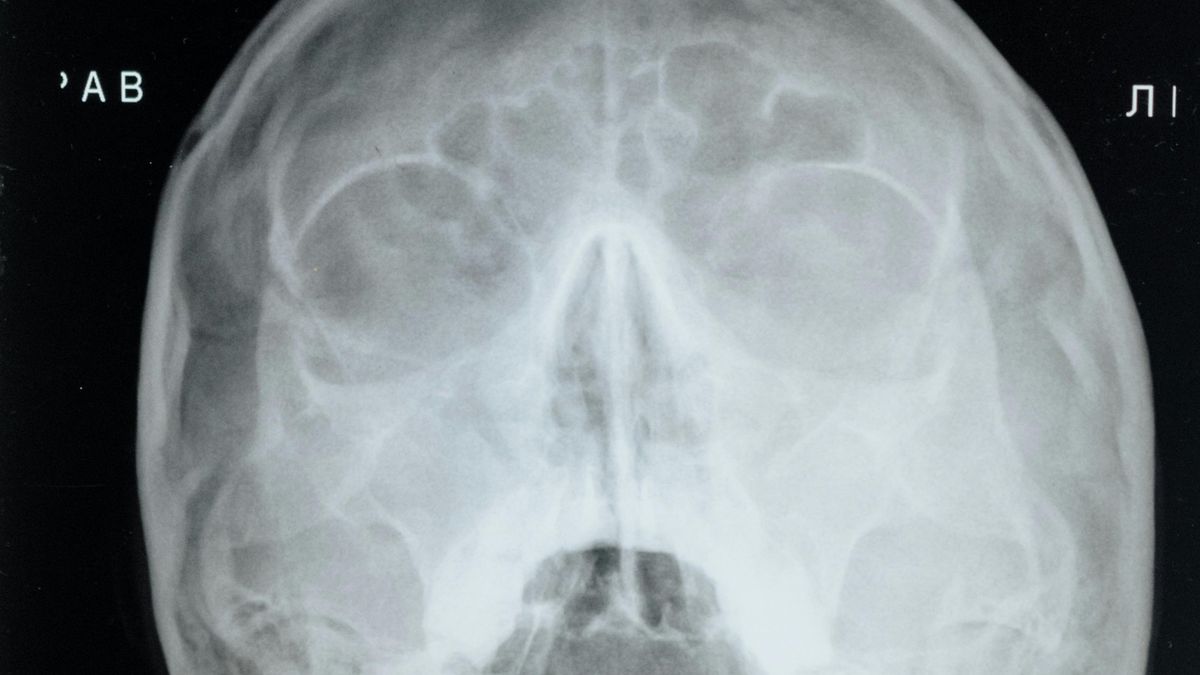

V muzeu je k vidění přibližně 250 preparátů – tekutinové i kostěné – které představují patologicky změněné lidské orgány. Například plíce kuřáka, cirhotická játra, zbytnělé srdce, nádory mozku, zánětlivé změny, vrozené vývojové vady, vzorky pravých neštovic, atd. Z první světové války jde o různá střelná poranění, zkřivení kostí anebo například o ruskou střelu, která zůstala v páteřním kanále. Patologická sbírka představuje různé nemoci - od žlučníkových kamenů přes cystu na vaječníku až po zaprášené plíce.